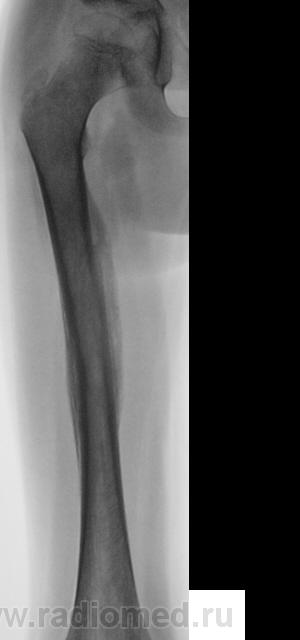

Пациент направлен на конрольное рентгенологическое исследование средней трети бедренной кости с целью оценки консолидации. Ранее - первичный снимок пациент был направлен на рентгенографию средней трети бедра, что и было сделано. Но, при производстве "контроля" рентгенолаборанты захватили тазобедренный сустав в прямой проекции, и возникли неясные сомнения по поводу головки, да и вообще...

Отлично все срослось. А что не нравится в головке? Остеопороз? Может быть после длительной иммобилизации.

Сама головка не нравится, особенно её нижне-медиальный отдел.

Интересная дискуссия. Жаль с опозданием увидел (однако же, много времени уходит, пока всё на сайте просмотришь). На мой взгляд, патологии головки нет, без фрагментации, проекционно пересекается с тенью обызвествляемого Y-хряща. Под головкой медиально, несомненно, есть остеопороз, придающий нечеткость картине. Впрочем, регионарный остеопороз имеет место вследствие закономерной атрофии после иммобилизации. Сюда же наслаивается субстрат т.н. фигуры серпа, еще не оформленный. Впадина нормальная. Кость срослась - замечательно, всем бы такие результаты. Реабилитация обязательна.